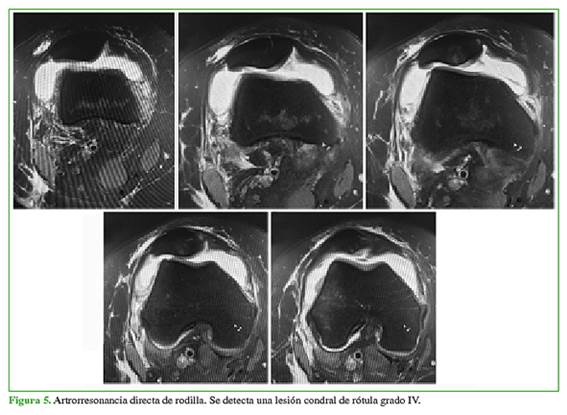

Mujer de 55 años, enfermera, con dolor crónico de origen rotulofemoral de la rodilla derecha secundario a una fractura osteocondral de la rótula luego de un accidente laboral. En febrero de 2017, fue sometida a dos plugs de OATS (Osteochondral Autograft Transplantation Surgery [sistema de transferencia de autoinjerto osteocondral]) en la rótula, con evolución estacionaria, a pesar de la rehabilitación y los arcos de movilidad completos. En septiembre de 2017, se le realizó una viscosuplementación con hialino (Synvisc-One®); el dolor anterior de rodilla no mejoró, persistía la limitación para caminar en superficies inclinadas y tenía crepitaciones permanentes. En

octubre de 2017, la artrorresonancia directa de rodilla mostró una lesión condral grado IV de la rótula (Figura 5).